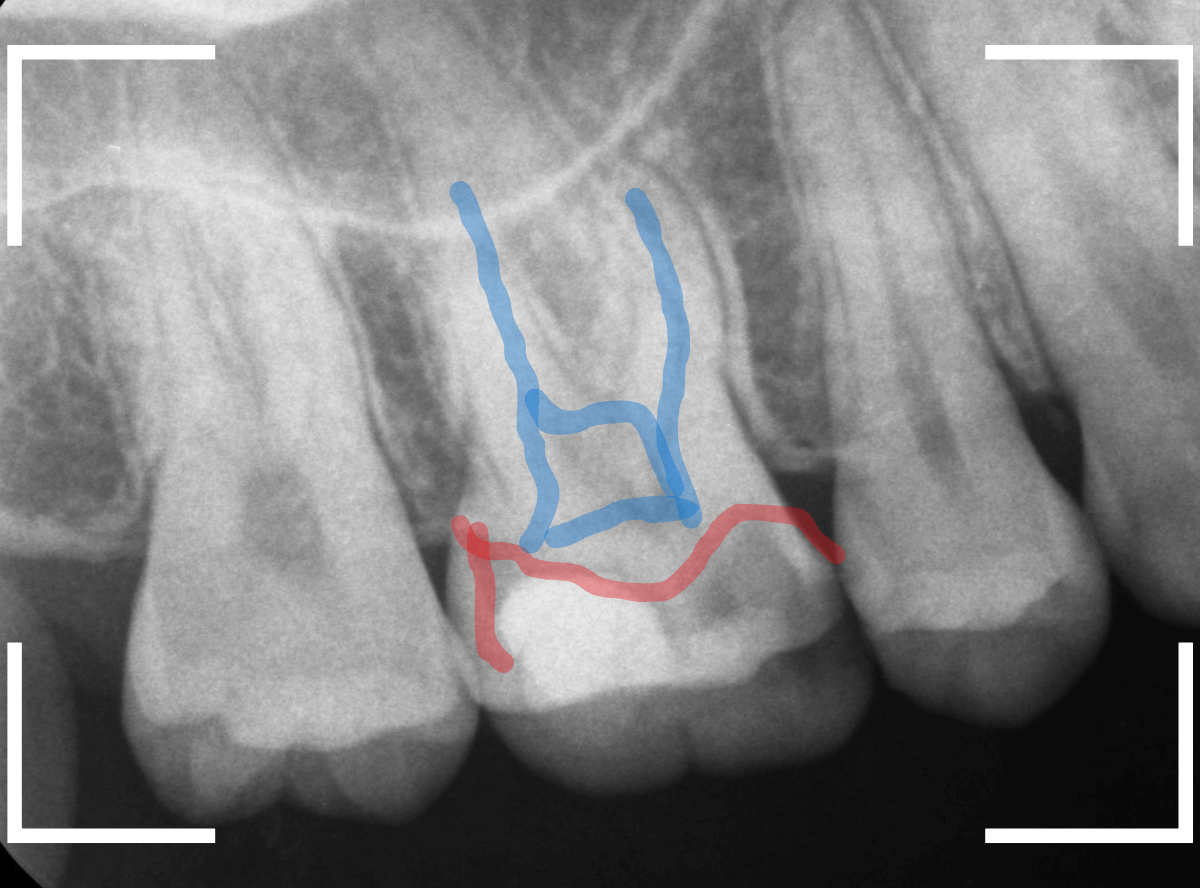

レントゲン写真で確認します。

青い線が歯の神経、赤い線が虫歯です。

おやしらずがあった際にはわかりづらかったですが、歯の後ろ側のおやしらずが重なっていたところが虫歯になっているのがわかります。

おやしらずが原因で、このように手前の歯が虫歯になってしまう事が多いために、抜歯を勧められる事が多いのです。

そして、虫歯の部分におやしらずが被さっていたために、しみる症状などを感じなかったのです。